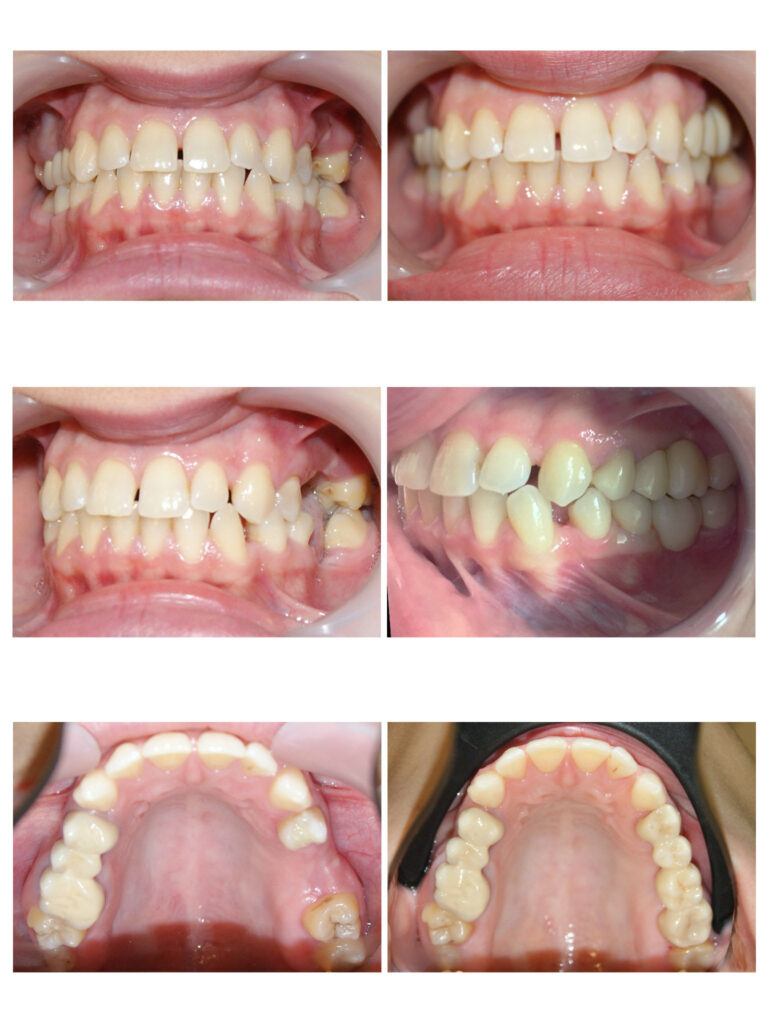

Întrebare “Ce se întâmplă dacă îmi vor fi extrași dinți buni? “Răspuns “Spațiile vor fi închise complet! “ DA, DA, DA! Adesea trebuie să facem extracții în scop ortodontic pentru a crea spațiul necesar alinierii dinților care rămân pe arcadă. În aproximativ 2 ani de tratament ortodontic dinții migrează și închid spațiile astfel încât vei uita că acolo au mai fost vreodată alți dinți